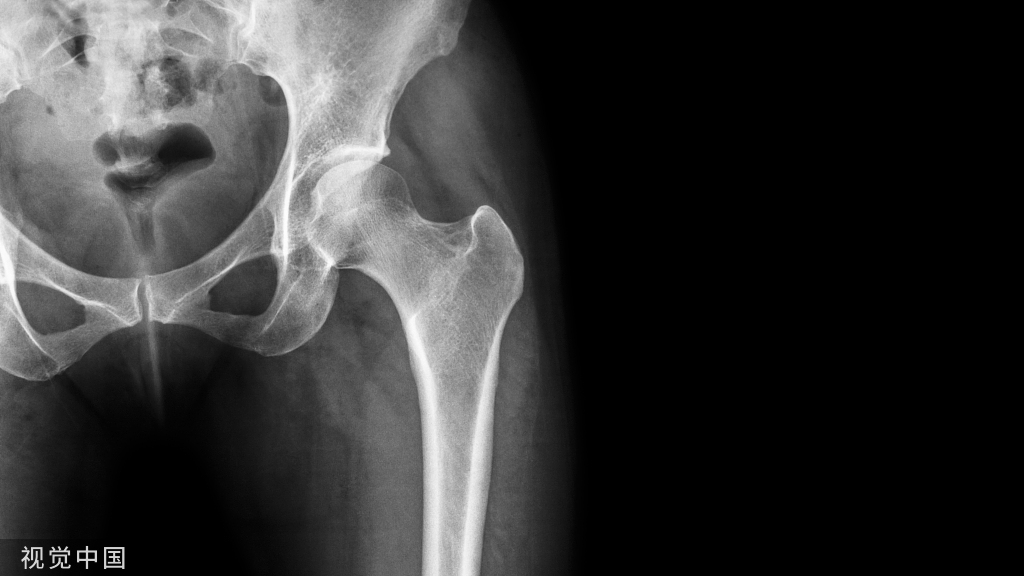

3、股骨颈截骨

脱位髋关节,然后进行股骨颈清理,包括股骨截骨部位。测量股骨头中心至小粗隆的距离(LOC),标记截骨线,一般位于小粗隆上1.5cm左右。

细节:可让助手在对侧进行截骨,这样便于操作,确保截骨面平行。同时注意截骨时避免大粗隆损伤。

股骨颈截骨